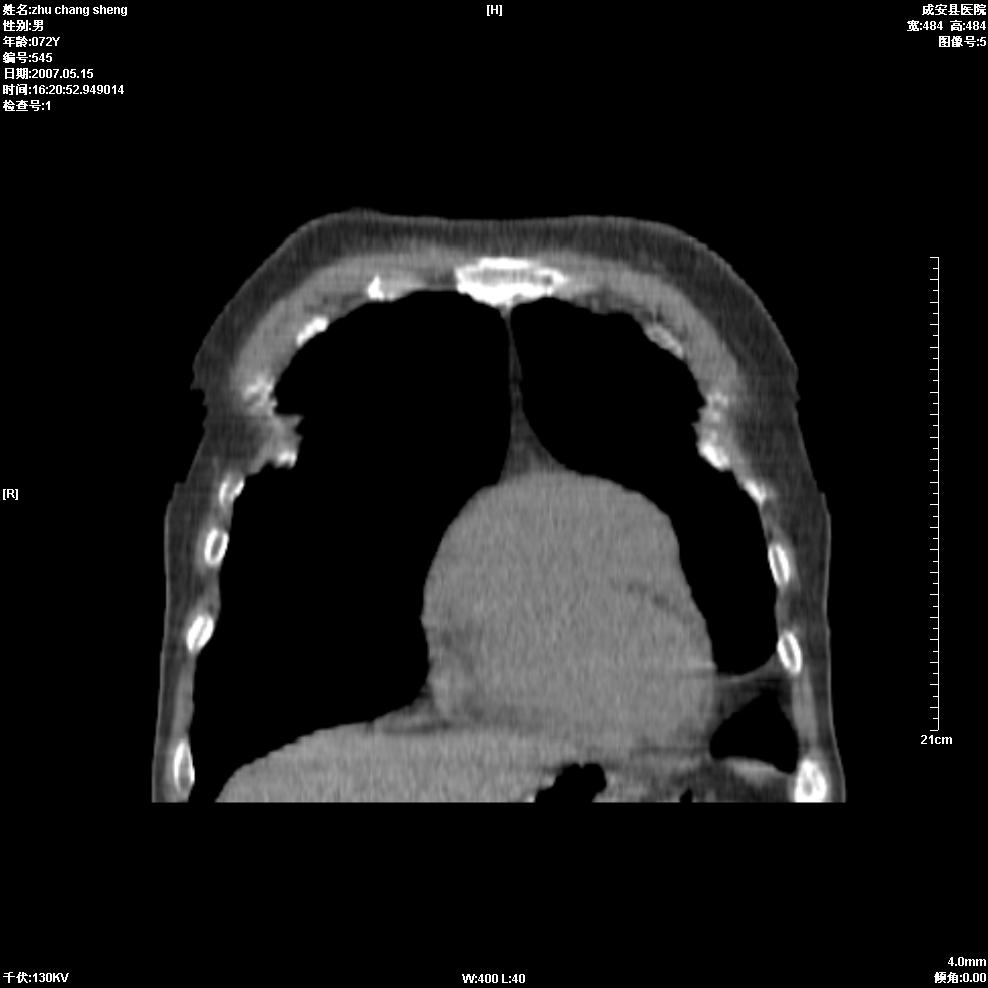

以下是引用医博云天在2007-5-15 19:10:00的发言:[br]心包积液,胸腔积液,心影增大,左心为主。

以下是引用zhangzhongshou在2007-5-15 20:21:00的发言:[br]心包积液可以肯定有,肿块显示不清,建议增强或mri检查。

以下是引用jinning在2007-5-15 21:06:00的发言:[br]心包积液可以肯定,建议增强或mri检查吧!

以下是引用拾荒者在2007-5-15 22:28:00的发言:[br]心包膜增厚,有少量积液,右室前壁示均匀软组织密度影,边界欠清,建议增强扫描或mri检查与室壁瘤鉴别。

以下是引用还珠格格在2007-5-19 9:50:00的发言:[br]病人与5月18日 做了核磁增强扫描 确诊为前上纵隔侵袭性胸腺瘤。